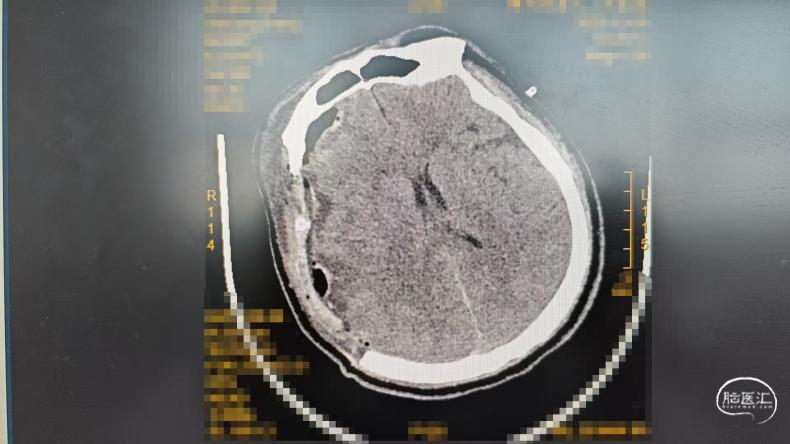

颅骨修补术前CT:

颅骨修补术中照片: